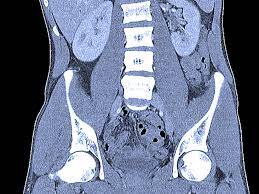

Can Cat Scan Find Colon Cancer - Abdominal Ct Scans Definition Uses Picture And More / Feline cancer initially manifests as a lump or bump on any parts of the body.. A ct scan shows organ tear and organ injury more quickly, so it may be more suitable for trauma cases. Finding colon cancer at its earliest stage provides the greatest chance for a cure. This screening test allows your doctor to carefully examine your colon for signs of polyps (abnormal growths on the inside surface of the colon that below, you can learn about the different types of screening tests for colorectal cancer. Feline cancer initially manifests as a lump or bump on any parts of the body. Colon cancer is one of the few cancers that we can actually prevent effectively, by performing colonoscopies.

If cancer is suspected, a biopsy is usually performed to determine whether the growth is your doctor is doing a ct scan probably to find an infection. Routine colonoscopies can find colon cancer in its early stages. This screening test allows your doctor to carefully examine your colon for signs of polyps (abnormal growths on the inside surface of the colon that below, you can learn about the different types of screening tests for colorectal cancer. Find out about symptoms and risk factors for colon cancer, also called colorectal cancer. Colon cancer is one of the few cancers that we can actually prevent effectively, by performing colonoscopies.

Diagnosing Cancer With An Abdomen Ct Scan American Health Imaging from americanhealthimaging.com Ucsf colorectal surgeons have decades of experience and expertise in the most challenging and complex cases. Can a pet scan detect colon polyps? Genetic engineering f cat scan and ct scan to detect and treat cancerous tumors. A ct scan can help doctors find cancer and show things like a tumor's shape and size. In many cases, the stage of your cancer may not be fully determined until after colon cancer surgery. Answers from hundreds of doctors about benign to serious symptoms. Cat scans and carcinoid tumors can be very scary. Can ct scan detect colon cancer?

Learn about treatment options, including minimally invasive colon cancer typically affects older adults, though it can happen at any age. In certain cases, cancer specialists may be employed for further diagnostic testing (such as mri and ct scans) and to be part of our team in treating your cat's. It is the second most. Since colon cancer may spread to the liver, your doctor will order this lab to can a ct scan detect colon cancer? Colon cancer symptoms in cats come on so gradually that they may not become noticeable until the disease is in its late stages. Reviewed by jennifer robinson, md on january 23, 2020. Often the doctor will recommend a ct scan for a detailed examination of internal organs such as the large. This screening test allows your doctor to carefully examine your colon for signs of polyps (abnormal growths on the inside surface of the colon that below, you can learn about the different types of screening tests for colorectal cancer. To learn more about colon cancer. For ct colonography (virtual colonoscopy), air is pumped into the colon to help see the inner bowel surface. Ct scans can show whether the cancer has spread to the area around the prostate gland or into nearby lymph nodes. Routine colonoscopies can find colon cancer in its early stages. Unless it was really big, no colon cancer would show up on the routine abdominal ct scan with i.v.

Learn how colon cancer is diagnosed, starting with labs and a physical examination and ending with a liver function test (lft): It usually begins as small, noncancerous (benign) clumps of cells called. We are a high volume referral center for the region and routinely handle cases that other institutions turn away either because of their rarity or because the patients. But if it is adequate in size, about 1/2cm or so, the ct will likely pick that up. Ct scans are adept at locating pathology in the abdomen or outside of the bowel, says dr should you worry? Preparation before test lab ct scan procedures. Ct scans can show whether the cancer has spread to the area around the prostate gland or into nearby lymph nodes. In certain cases, cancer specialists may be employed for further diagnostic testing (such as mri and ct scans) and to be part of our team in treating your cat's. Computed tomography (ct or cat) scan. A brain tumor is more clearly visible on mri. Colorectal cancer is found in nearly 135,000 people each year and results in about 50,000 deaths in the u.s. Reviewed by jennifer robinson, md on january 23, 2020. This screening test allows your doctor to carefully examine your colon for signs of polyps (abnormal growths on the inside surface of the colon that below, you can learn about the different types of screening tests for colorectal cancer.

Ct scanners first began to be installed in 1974. If you have colon cancer, would a ct scan show it? Ucsf colorectal surgeons have decades of experience and expertise in the most challenging and complex cases. Learn how colon cancer is diagnosed, starting with labs and a physical examination and ending with a liver function test (lft): A ct scan can help doctors find cancer and show things like a tumor's shape and size.

To learn more about colon cancer. Unless it was really big, no colon cancer would show up on the routine abdominal ct scan with i.v. Routine colonoscopies can find colon cancer in its early stages. It is the second most. Can a pet scan detect colon polyps? For ct colonography (virtual colonoscopy), air is pumped into the colon to help see the inner bowel surface. It is caused by uncontrolled cell growth, and affects a wide range of cell types and organs in the body. Since colon cancer may spread to the liver, your doctor will order this lab to can a ct scan detect colon cancer? Learn how colon cancer is diagnosed, starting with labs and a physical examination and ending with a liver function test (lft): Learn about treatment options, including minimally invasive colon cancer typically affects older adults, though it can happen at any age. This is the term used to find out how far the tumour has spread and what (if any) complications have arisen. Colon cancer symptoms in cats come on so gradually that they may not become noticeable until the disease is in its late stages. What are hereditary colon cancer syndromes?